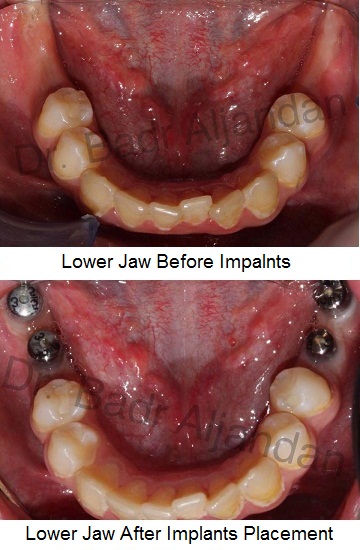

غرسات الأسنان مصنوعة من مادة التيتانيوم. توضع داخل عظام الفك في نفس مكان الأسنان المفقودة. الجزء المعدني الموجود داخل عظام الفك يعمل كوتد بديلا لجذر الأسنان. يتم تركيب الجزء المعدني بواسطة عملية جراحية داخل الفك. وبعد فترة يتم ترابط عظام الفك مع الجزء التيتانيوم مسببا تثبيت قوي للجزء الصناعي داخل الفك. الجزء الأوسط يثبت وتد قوي للأسنان الصناعية.

فريق عمل كامل يقوم بمجهود مشترك من جراحي الوجه و الفكين و الاستعاضة الصناعية في طب الأسنان هم يقومون بعمل غرس الأسنان. من الممكن بعد خلع الأسنان الاحتياج لعمل اعادة وضع عظام حسب الضرورة. طبيب الاسنان (الاستعاضة) يقوم يتثبيت الجزء العلوي من الغظاء الخارجي للغرسة. أيضا يتم عمل دعامات صناعية مؤقتة اثناء اجراء عملية الغرس.

مراحل تركيب الغرسات (الزرعات) من الأوتاد إلى الأسنان الصناعية